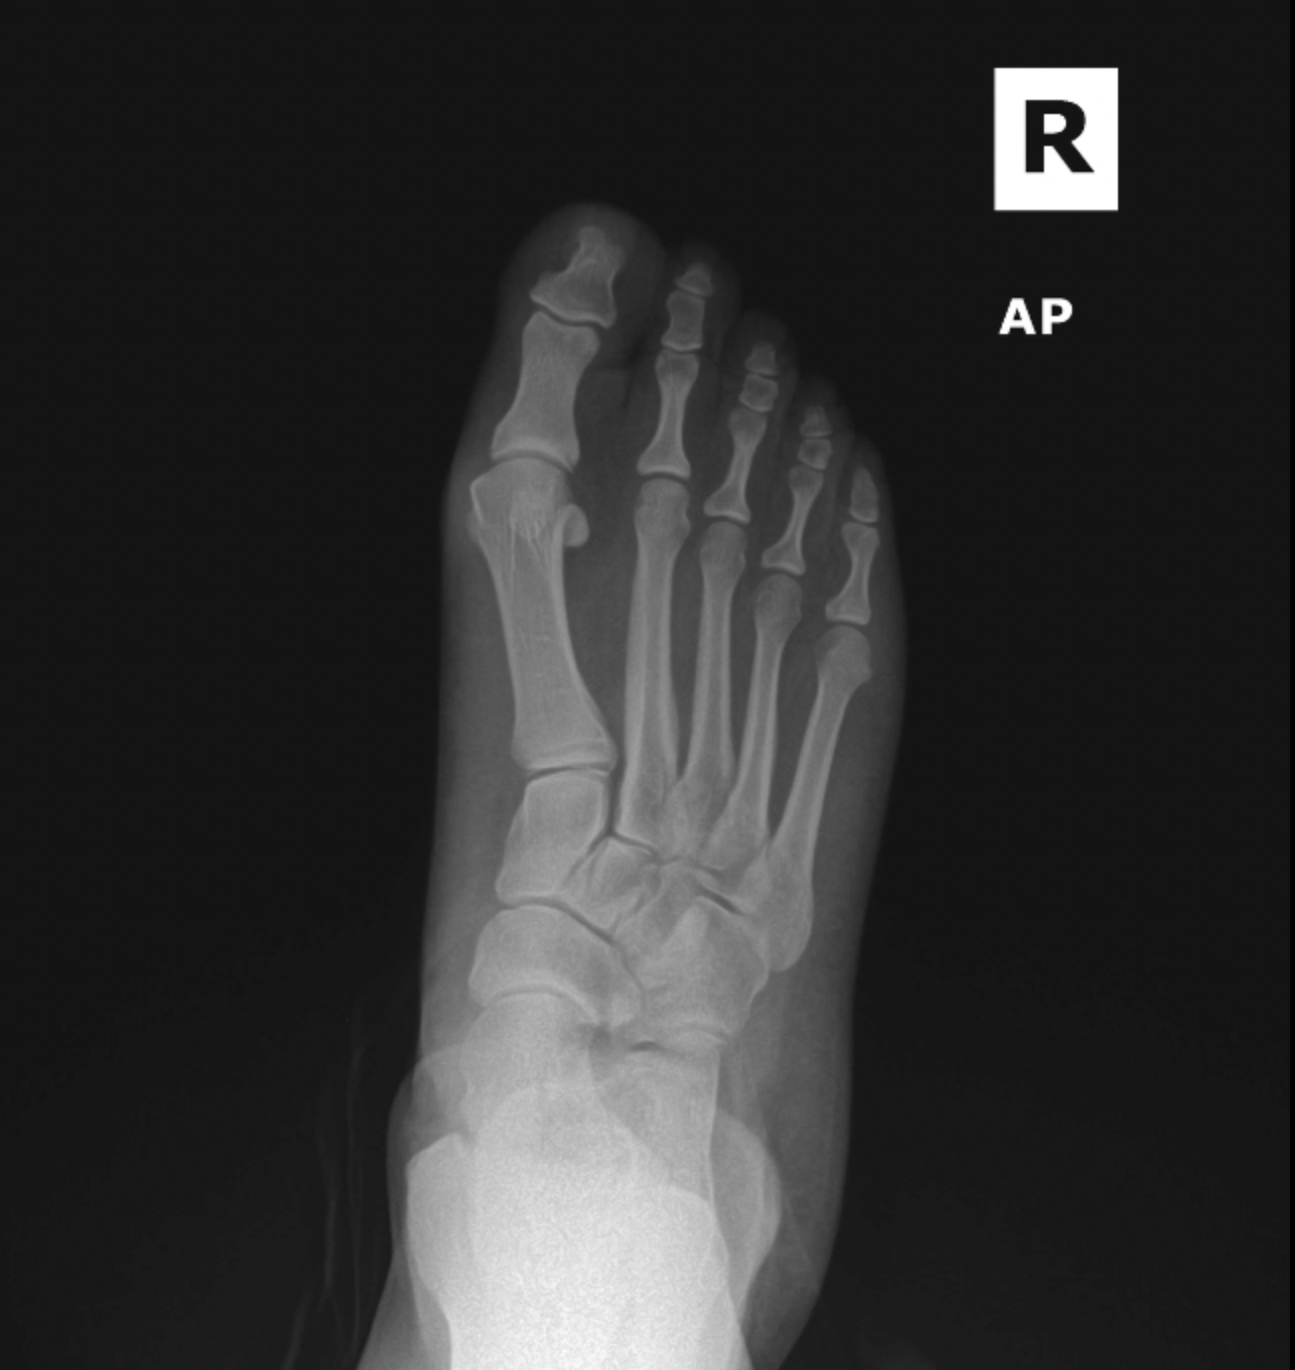

MIS Bunion

MIS3

MIS2